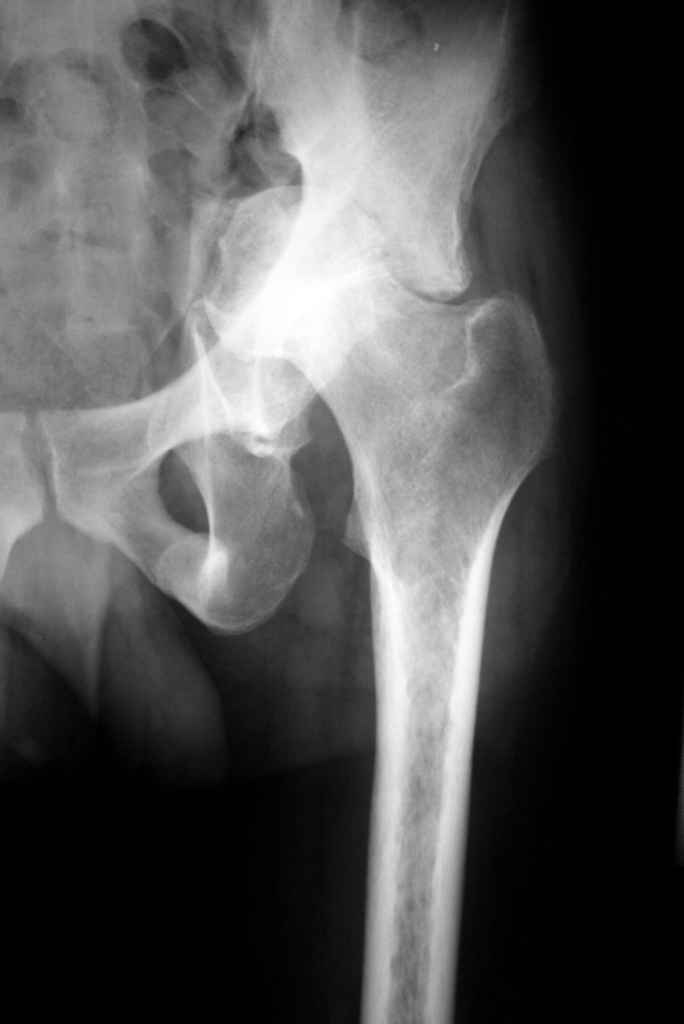

К нам обратился житель Казахстана с застарелым вывихом бедра. Травма год назад, вместо синтеза заднего края казахскими умельцами установлена клинковая пластина, через 6 мес удалена. Больной ходит с тростью,сгибание в т-б 90, разгибание 170, укорочение 5 см, боли не выражены, анальгетиками не пользуется. Настроен на эндопротезирование в клинике, где есть опыт подобных операций (возможно за рубежом).Наш план: аппарат таз-бедро, постепенное низведение бедра, "октопус" с пластикой. Но с такими большими дефектами мы не сталкивались.Есть вариант сначала аппарат, затем реконструкция впадины, протез обычный через 4-6 мес.Есть мнение не восстанавливать длину. Будем признательны за полезные советы. Было бы интересно посмотреть пример.

Прилагаю в качестве иллюстрации одну из последних операций.

С уважением, Р.Тихилов

Еще одно наблюдение, неправильно сросшийся перелом заднего отдела ВВ с ввихом головки бедра 16-и летней давности.

Кстати, судя по рентгенограммам и КТ истинная разница в длине ног не столь велика, укорочение, главным образом, за счет контрактур.